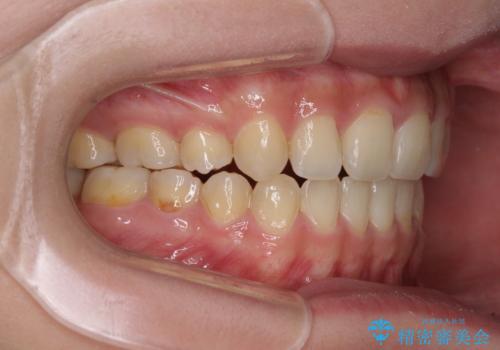

話しにくいオープンバイト ワイヤー装置による抜歯矯正治療

- 前歯のオープンバイトを気にして来院された患者様です。

上下前歯の前後位置が大きくずれていたため、上顎左右第一小臼歯2本を抜歯してワイヤー装置による矯正治療を行うこととしました。

オープンバイトの原因は舌の突出癖であり、癖が改善されないと治療経過に影響を及ぼすため、舌のトレーニングを指示しました。